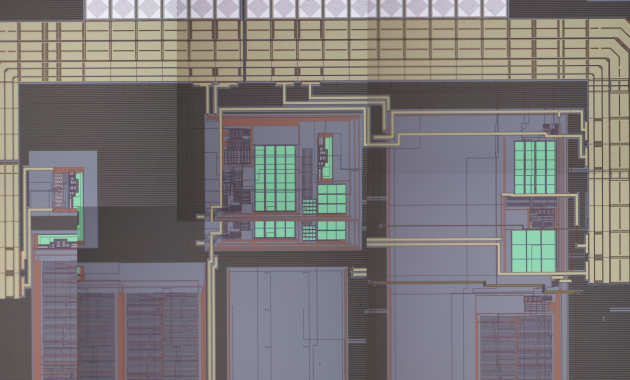

We are developing a new generation of neural interface to provide an innovative treatment for people who suffer from overweight and obesity.

We are developing a new generation of neural interface to provide an innovative treatment for people who suffer from overweight and obesity.